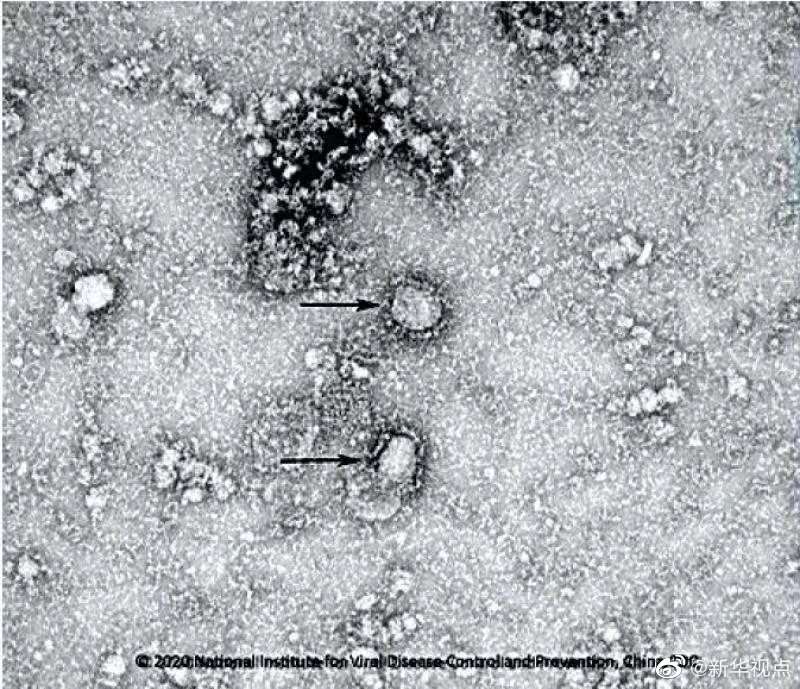

國家病原微生物資源庫于2020年1月24日發布了由中國疾病預防控制中心病毒病預防控制所成功分離的我國第一株病毒毒種信息及其電鏡照片、新型冠狀病毒核酸檢測引物和探針序列等國內首次發布的重要權威信息,并提供共享服務。看病毒“真容”↓↓↓(記者田曉航、王秉陽)